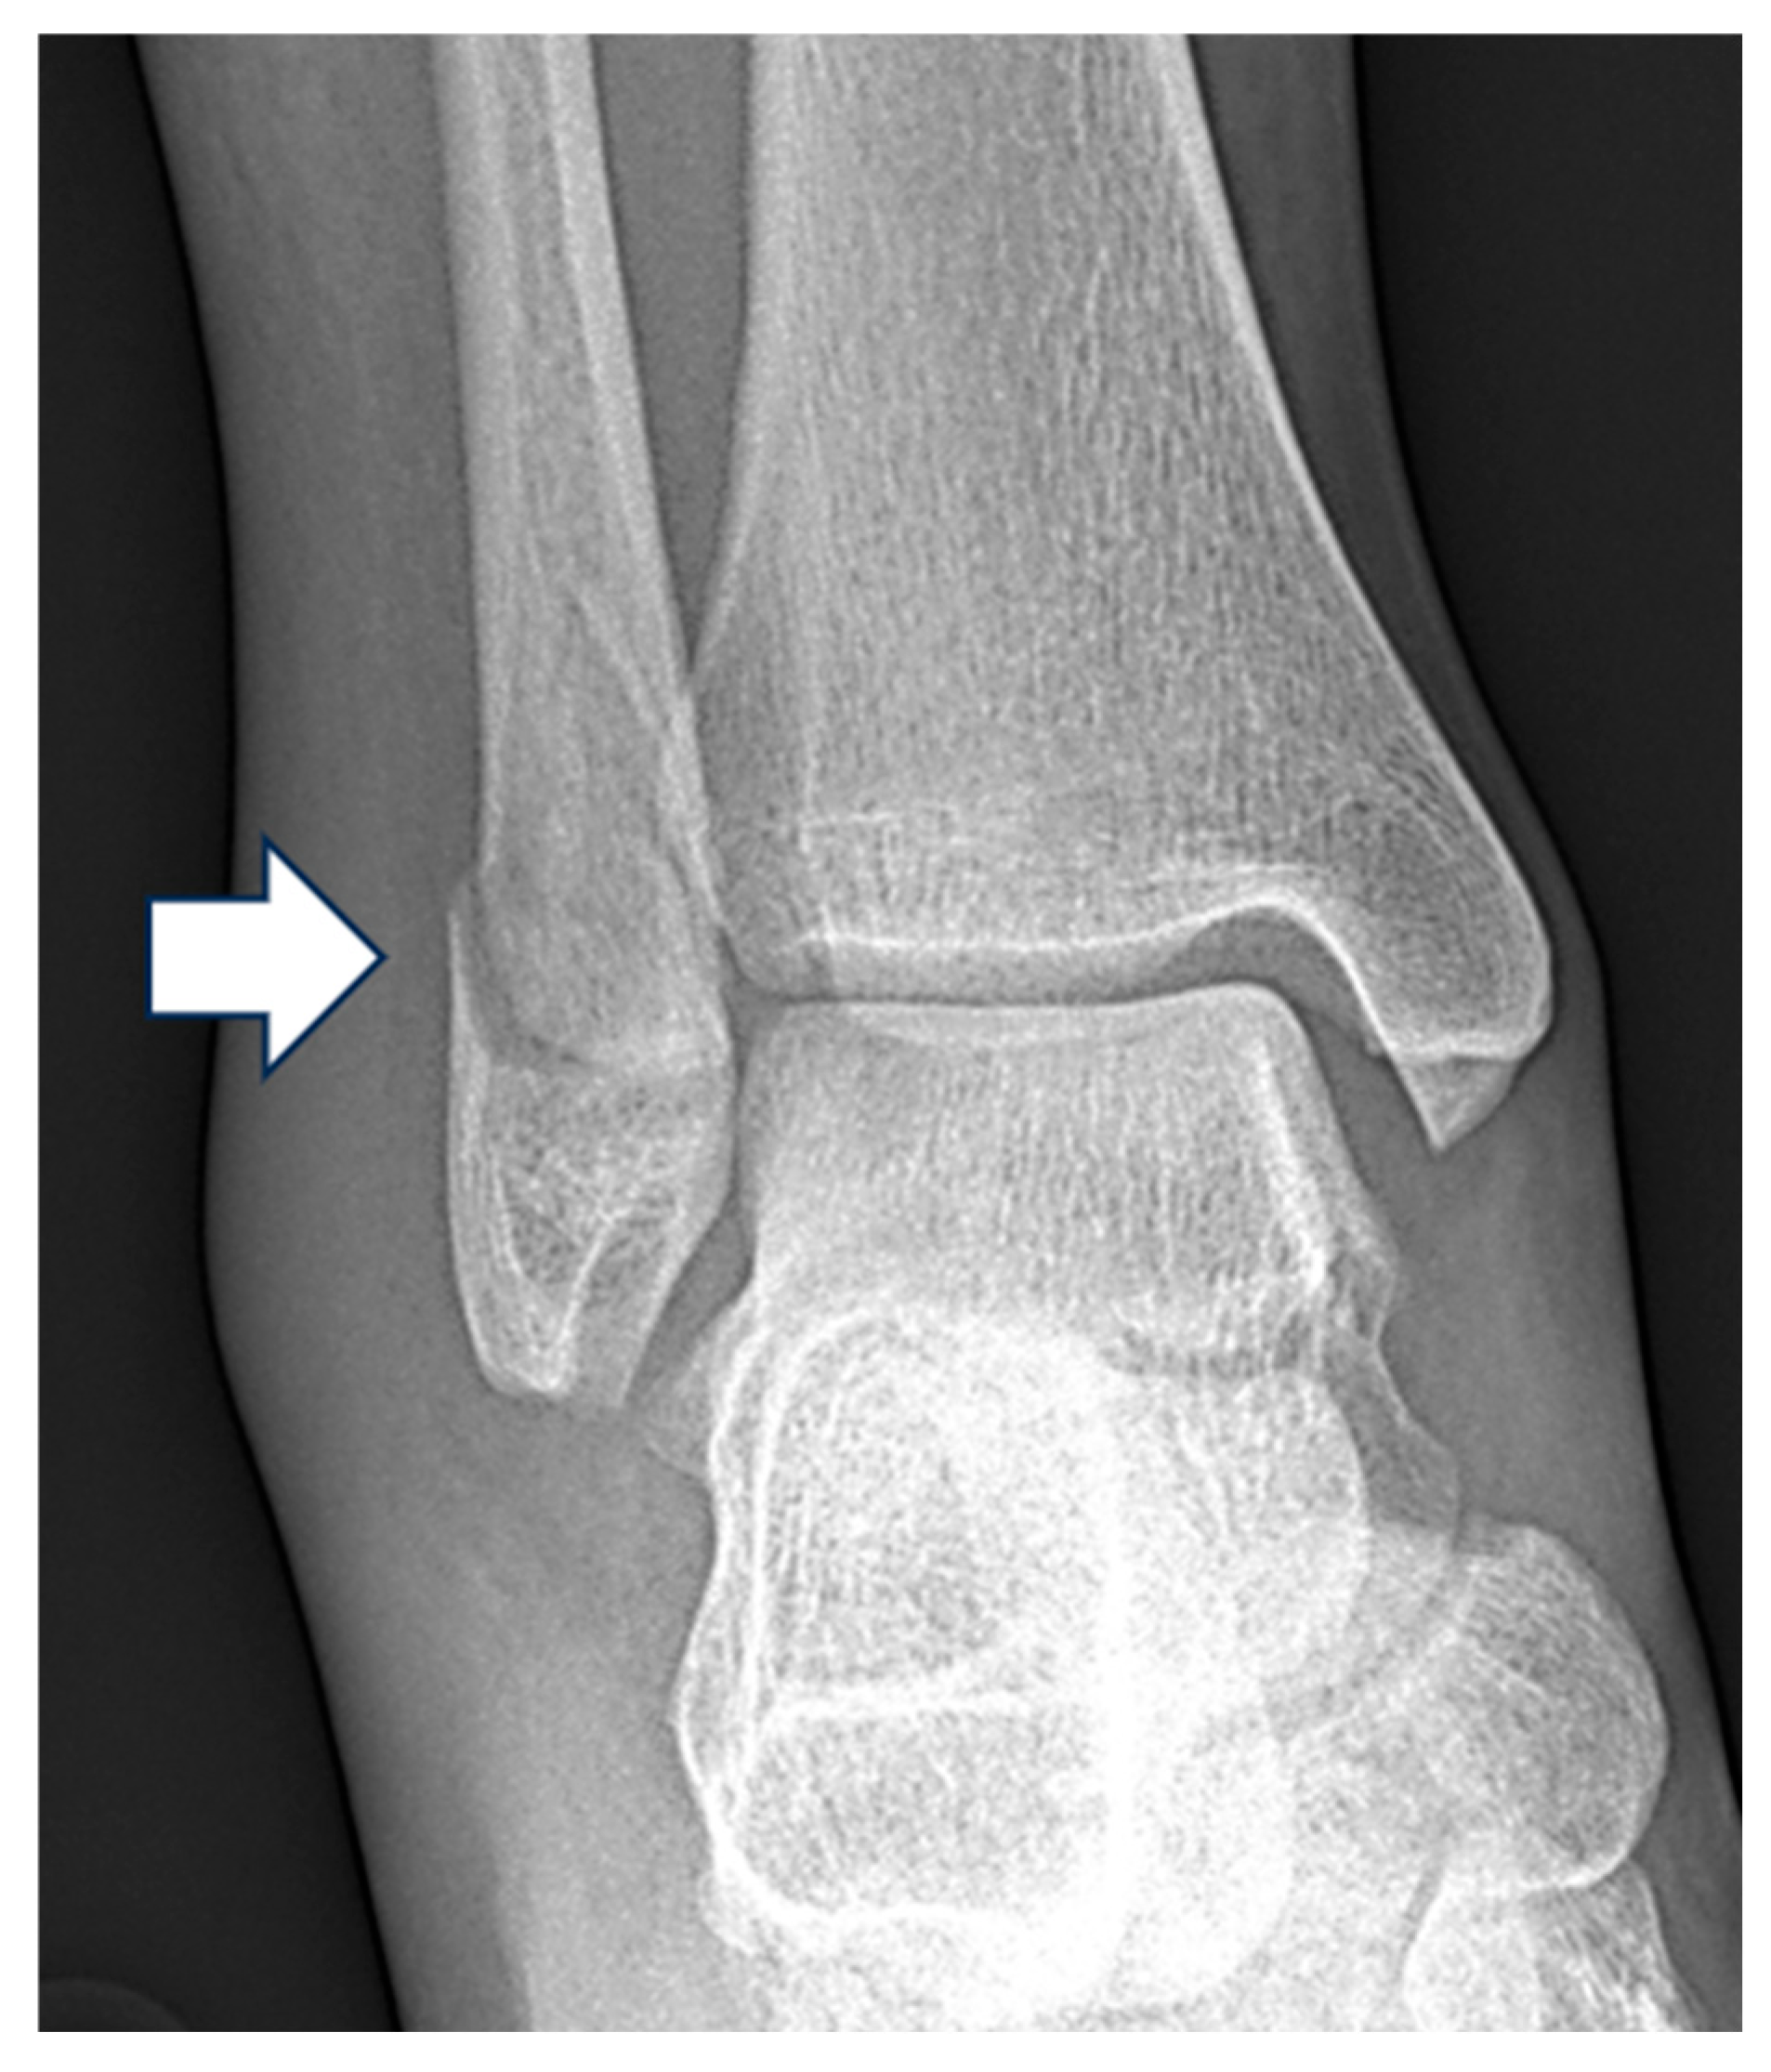

| Pattern (n) | Measurement | Mean ± Standard Deviation (mm) |

|---|---|---|

| Weber A (127) | Medial Clear Space | 3.3 ± 1.1 |

| Lateral Clear Space | 4.2 ± 1.4 | |

| Superior Clear Space | 3.4 ± 0.7 | |

| Weber B (216) | Medial Clear Space | 4.4 ± 2.4 |

| Lateral Clear Space | 4.4. ± 1.5 | |

| Superior Clear Space | 3.6 ± 0.7 | |

| Weber C (130) | Medial Clear Space | 5.7 ± 3.6 |

| Lateral Clear Space | 5.8 ± 2.9 | |

| Superior Clear Space | 3.7 ± 0.9 |

| Pattern (n) | Medial Clear Space | Frequency |

| Weber A (127) | <4 mm | 90 (70.9%) |

| 4–5 mm | 33 (26.0%) | |

| >5 mm | 4 (3.1%) | |

| Weber B (216) | <4 mm | 97 (44.9%) |

| 4–5 mm | 83 (38.4%) | |

| >5 mm | 36 (16.7%) | |

| Weber C (130) | <4 mm | 32 (24.8%) |

| 4–5 mm | 58 (45.0%) | |

| >5 mm | 39 (30.2%) |